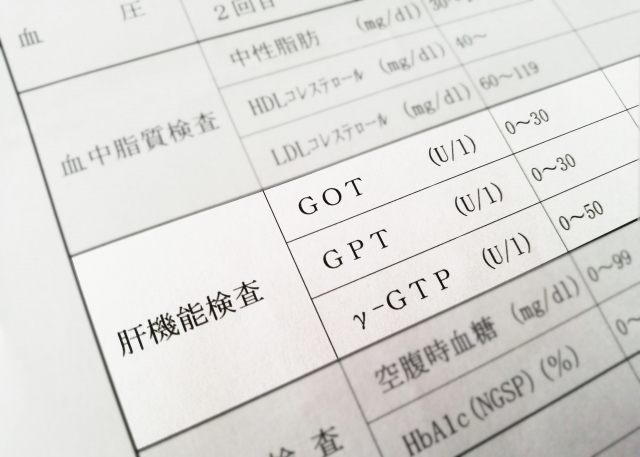

肝機能の検査数値 「AST」 「ALT」 「γGTP」とは?

まずはよく健診で測定されている肝機能を示す項目を解説します。

AST(以前はGOTと表記)

肝臓の細胞の中にある酵素。肝臓の細胞が壊れると血液に漏れ出てくるので数値が上昇します。

肝臓以外に、心臓や筋肉、腎臓などの細胞にも含まれており、数値が上昇しても肝臓からかどうかはわかりません。

血液中で存在できる時間は約11-15時間程度であり、細胞が壊れなくなると1日で数値が下がっていきます。

ALT(以前はGPTと表記)

こちらも肝臓の細胞の中にある酵素。主に肝臓の細胞にしかないため、上昇した場合は肝臓の細胞が壊れていると考える証拠になります。

血液中で存在できる時間は約40-50時間と長めであり、数値が高い状態が持続しやすい特徴があります。

γGTP

肝臓の中にある胆管の細胞に多く存在し、胆管の機能に異常があると上昇しやすい。

胆管の中を流れる消化液の胆汁がうまく流れなかったり、胆管が詰まったりする場合でも上昇します。

もう一方の特徴にアルコールや薬剤の影響で過剰に作られることがあり、肝臓にダメージがなくても数値が上昇することがあります。

アルコールを飲むと、数日から数週間かけて徐々に上昇していき、禁酒を二週間以上すると徐々に数値が下がっていきます。

AST・ALTは肝臓の細胞が壊れている可能性をあらわし、γGTPは胆管の機能の低下、もしくはアルコールなどによる影響があるか といった意味合いになります。